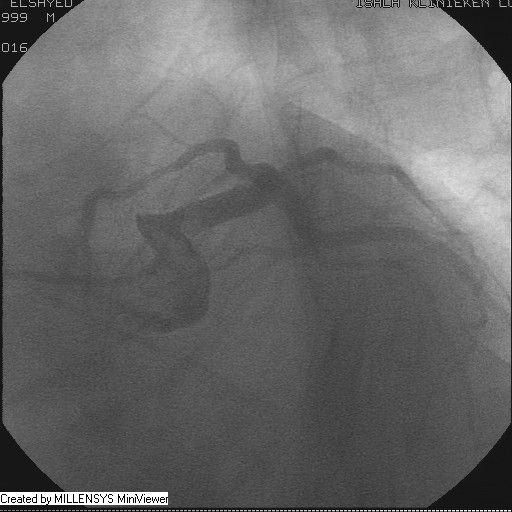

Patient transfered to Cardiac Catheterization Laboratory, coronary angiography showed atherosclerotic coronaries but without significant lesions, especially LAD that was patent with TIMI 3 flow (Figure 1- 5). Re-evaluation of the Angiography showed a small stump that can be for an occluded 1st diagonal (Figure 2a), at that level the LAD has a non-significant lesion.

Figure 1

Figure 2